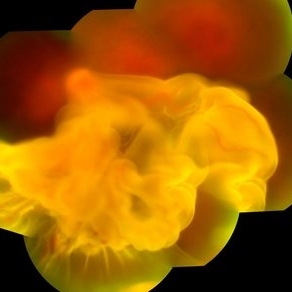

Choroid hemangioma

Patient 54 years old, Female, progressive loss of vision. In the multimodal evaluation of the retina showed important retinal alterations. A discreet opacity of the media impairs the quality of the images. In the Autofluorescent Background Image with a green filter, because it reaches a depth in the retinal tissue, it is able to show changes that affect the retinal pigment epithelium, it was better in this case than with the green filter. WF retinography shows an elevated, slightly reddish lesion, probable serous retinal detachment, mobilization of pigments and phantom vessels.

Photographer: JEFFERSON ROCHA DE SOUSA - Retinal Department at Instituto Dr. Suel Abujamra Sao Paulo-Brazil

Imaging device: Clarus 700 - Zeiss 135 degree images. Multimodal Evaluation

Condition/keywords: elevated retinal lesion, hemangioma, melanoma, serous retinal detachment